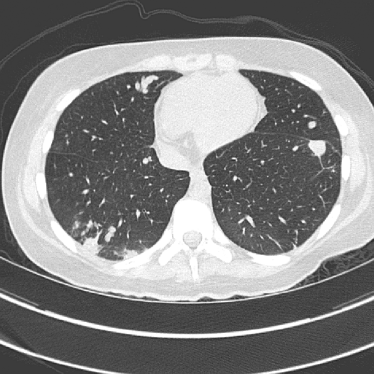

Figure 14: Qualitative clinical results from a thoracic CT staging dataset for a 12-year-old with osteosarcoma with pulmonary metastases. The clinical standard hybrid IR is shown on the left and JENG is on the right. (a) The clinical standard hybrid IR in lung window with a window center of -600 HU and a window width of 1500 HU. (b) JENG at a resolution comparable to the clinical standard, but with less noise and fewer artifacts. (c) The clinical standard hybrid IR in soft tissue window with a window center of 55 HU and a window width of 440 HU. A metastatic lung cancer nodule can be found in the left upper lobe. (d) JENG in soft tissue window at a comparable resolution, but with less noise and fewer artifacts. Note that JENG is not fully corrected for beam hardening artifacts.

V.B. Clinical Cases

None of the spatial resolution and artifact reduction advantages would hold unless JENG shows image quality improvement over the clinical standard method on patient datasets. To do so, we evaluated JENG on 5 thoracic and 3 abdominal CT scans and all scans used the same parameter settings as those for the ACR phantom scan, except that the tube current and the pitch is modulated individually for each patient. The exact experiment setup was discussed in Sec. IV.. For a fair image quality comparison, we matched the resolution of JENG and the clinical standard hybrid IR and studied their image noise and artifacts.